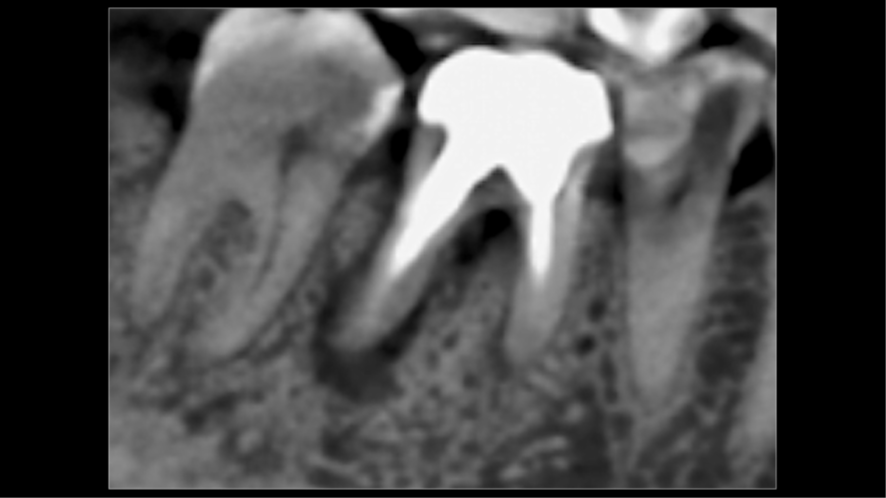

Mulher de 48 anos, sem antecedentes médicos relevantes, procurou atendimento odontológico com queixa principal de dor contínua em região do primeiro molar inferior direito. Na avaliação clínica foi observado uma fístula na vestibular do dente 46 (Figura 1) e a tomografia revelou uma fratura longitudinal, comprometendo a manutenção deste dente (Figura 2). Confirmada a necessidade de exodontia, foi planejada a instalação de um implante imediato e a confecção de um cicatrizador personalizado diretamente na plataforma do implante com um pilar provisório de titânio. Foi realizada uma extração dentária minimamente traumática visando preservar a integridade dos tecidos moles e duros circundantes (Figuras 3 e 4).